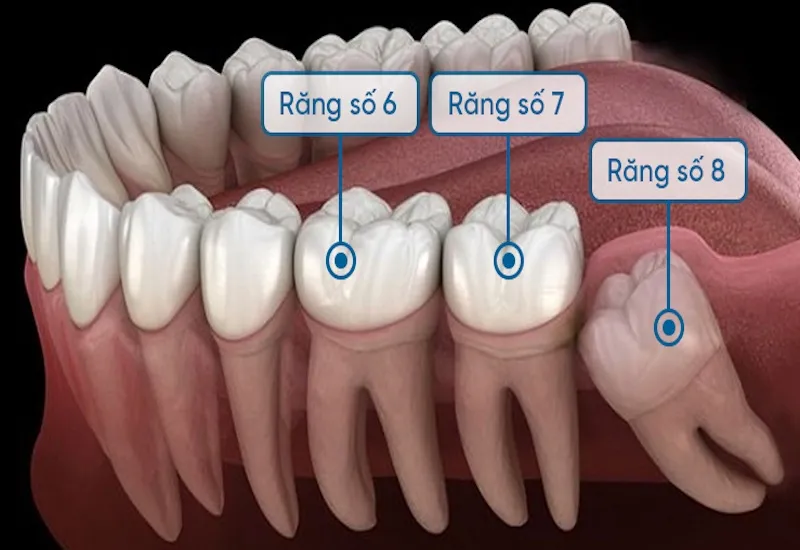

Trước khi biết răng số 7 bị sâu có nên nhổ không thì cần biết rõ về chiếc răng này. Ở người trưởng thành, bộ răng vĩnh viễn thường bao gồm 28 chiếc. Sau khi mọc đủ 4 chiếc răng khôn, tổng số răng sẽ là 32 chiếc. Trong đó, chúng ta có 4 răng số 7 đối xứng giữa hai hàm trên và dưới. Điểm đặc biệt của răng số 7 là cấu trúc chân răng khác nhau giữa hai hàm. Răng số 7 ở hàm dưới thường chỉ có 2 chân. Trong khi răng số 7 ở hàm trên có tới 3 chân. Từ đó giúp tăng khả năng chịu lực nhai.

Đây là chiếc răng có kích thước lớn. Nó đảm nhận chức năng quan trọng trong việc nhai và nghiền thức ăn. Răng số 7 cùng với răng số 6 chịu trách nhiệm chính trong việc nghiền nát thức ăn. Quá trình nhai của hai chiếc răng này không chỉ làm nhỏ thức ăn. Nó còn hỗ trợ trộn thức ăn với enzyme trong nước bọt. Từ đó giúp quá trình tiêu hóa ở dạ dày diễn ra hiệu quả hơn. Theo các chuyên gia, khả năng nhai của răng số 7 được đánh giá cao nhất trong hệ thống răng. Nổi bật hệ số 5, vượt trội hơn các răng khác.